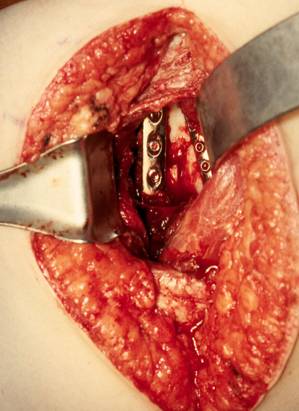

采用judet入路

电刀小心分离,由内向外

到肩袖处先用手钝性分离,然后小心切开,走肌间隙

如果实在需要暴露时,可部分切断,需要进行标记,术后重建

沿肩胛骨的骨板小心的剥离肌肉,进行显露

暴露骨折,复位骨折

拟行钢板内固定

先行普通螺钉进行加压,压住外侧钢板,然后进行锁钉固定

然后进行内侧的骨块固定

完成固定后,活动肩关节,确认螺钉没有进入关节

严密缝合肌肉夹板

术后